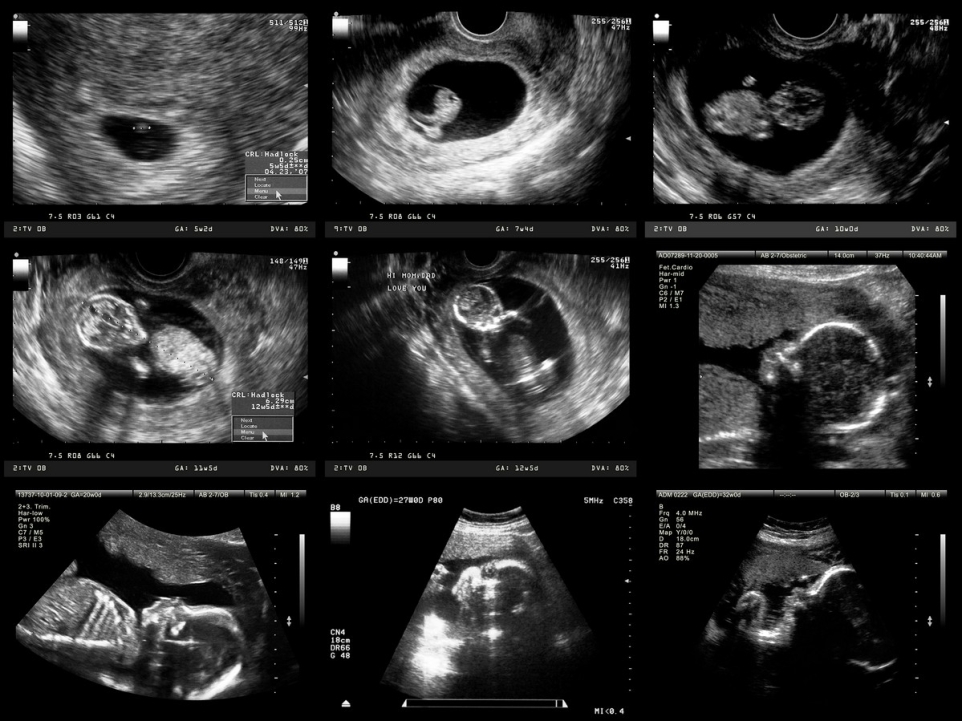

USG połówkowe jest kluczowym badaniem wykonywanym w II trymestrze ciąży, zazwyczaj między 18. a 22. tygodniem. To badanie ultrasonograficzne ma na celu ocenę anatomicznej budowy płodu oraz stałe monitorowanie zdrowia płodu, co umożliwia wczesne wykrycie ewentualnych nieprawidłowości rozwojowych i podjęcie odpowiednich działań.

USG połówkowe w ciąży obejmuje szczegółową ocenę wielu parametrów i struktur rozwijającego się dziecka. Lekarz wykonujący badanie analizuje m. in. biometrię płodu, w tym wymiar dwuciemieniowy (BPD), obwód głowy (HC), obwód brzucha oraz długość kości udowej. Oceniane są także wybrane elementy anatomiczne, takie jak fałd karkowy i obecność kości nosowej, które mogą stanowić markery niektórych zaburzeń genetycznych, w tym zespołu Downa.

Podczas badania w ciąży szczególną uwagę zwraca się na serce płodu, aby wykryć ewentualne wady układu krążenia, takie jak tetralogia Fallota czy ubytki w przegrodach serca. Badanie obejmuje również ocenę kręgosłupa, kończyn oraz innych narządów wewnętrznych, w tym mózgu, żołądka, pęcherza moczowego i nerek. Istotnym elementem jest ponadto określenie ilości płynu owodniowego oraz analiza położenia, grubości i struktury łożyska, co pozwala lepiej ocenić warunki, w jakich rozwija się dziecko.

USG połówkowe umożliwia wczesne rozpoznanie wielu wad wrodzonych i zaburzeń rozwoju. Badanie to jest pomocne w diagnozowaniu takich schorzeń jak wodogłowie, rozszczep wargi i podniebienia, przepukliny, nieprawidłowości ściany jamy brzusznej czy anomalie nerek. Dzięki temu możliwe jest szybkie zaplanowanie dalszej diagnostyki, a w wybranych sytuacjach także leczenia jeszcze w okresie prenatalnym lub tuż po porodzie.